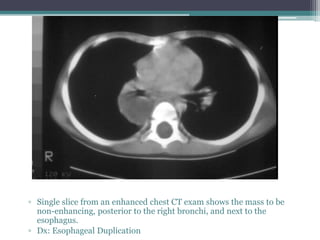

โ–ซ Single slice from an enhanced chest CT exam shows the mass to be

non-enhancing, posterior to the right bronchi, and next to the

esophagus.

โ–ซ Dx: Esophageal Duplication